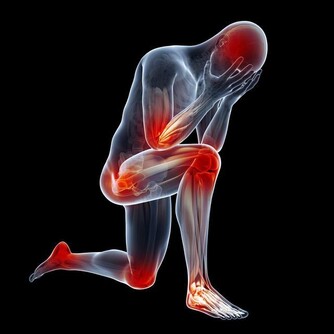

十、骶髂關節檢查?

盤腿試驗,又稱「4」字試驗,仰卧,將一隻腳向內彎曲放在另一側伸直的大腿上。請家人一手按住對側胯骨,另一手將屈曲的膝部往下壓,若臀部出現疼痛說明骶髂關節有病變。骶髂關節疾病是產生腰腿痛的常見原因之一,特別是老人腰腿痛多由此引發。